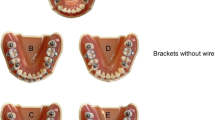

Study measurements

Manual diagnostic setup and printed digital diagnostic setup models were assessed by the modified American Board of Orthodontics Cast Radiograph Evaluation (ABO CRE) using ABO gauge. Seven out of eight criteria of the ABO CRE [25] were assessed: alignment, marginal ridge, buccolingual inclination, occlusal relationship, occlusal contact, overjet, and interproximal contact. Root parallelism, which needed a panoramic radiograph for the evaluation, was excluded. The modified ABO CRE assessment comprised various scores. The alignment score, which evaluates anterior and posterior teeth proper alignment, serves as the orthodontic setup main objective, affecting both teeth function and esthetics. The marginal ridge score evaluates the proper vertical level of the posterior teeth, cementoenamel junctions and interdental bone. The buccolingual inclination score evaluates the buccolingual inclination of the posterior teeth, which is essential to establish good occlusion, avoid balancing interferences and establish proper function. Occlusal contacts score evaluates the adequacy of posterior occlusion. The occlusal relationship score evaluates the anteroposterior relation of upper and lower posterior teeth using Angle’s relationship criteria. The overjet score evaluates the transverse relationship of the posterior teeth and the anteroposterior relationship of the anterior teeth, while interproximal contacts score checks whether the interproximal spaces between the teeth are closed.

To assess the quality of orthodontic treatment, a modified ABO CRE score was employed. Digital orthodontic diagnostic setup models were 3D printed, facilitating ABO CRE evaluation with an ABO measuring gauge. This approach was chosen based on previous research by Nguyen [31] and Okunami et al. [32] which demonstrated significant variability and inaccuracies in digital measurements of ABO-OGS.